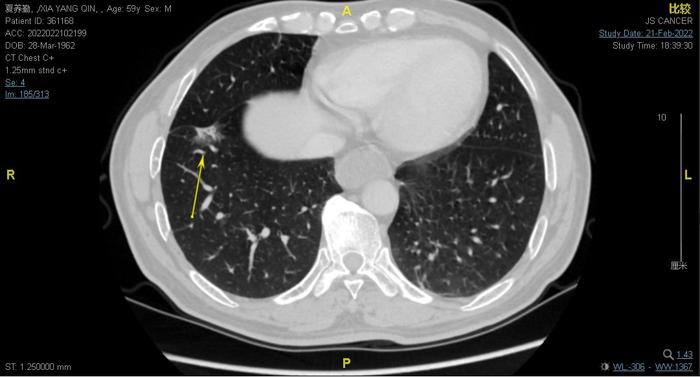

上图,此患者还有一个右下肺混合磨玻璃结节,恰好位于斜裂旁,引起斜裂胸膜凹陷

上图为提示此患者右下肺混合磨玻璃结节内部有少许实性成分,恰好位于斜裂旁,引起斜裂胸膜凹陷

这个混合磨玻璃结节比较大,病灶较大截面范围约20毫米×12毫米(肺窗测量)。看上去可以基本上判断为早期浸润性腺癌,也应该手术治疗。但是这个磨玻璃结节是次要病灶,比左下肺的主要的实质性肺癌生长缓慢的多,所以处于次要矛盾。左下肺的主要的实质性肺癌是主要矛盾,治疗效果基本上决定了患者的寿命。所以我,决定先进行左下叶肺癌的胸腔镜微创手术,加上左侧的纵隔淋巴结清扫术手术。术后靶向治疗或术后化疗。同时密切随访复查右下肺的混合磨玻璃结节有没有变化,只要有结节增大或内部密度升高就手术治疗。和家属反复沟通,告知家属,左下肺癌是主要矛盾,生长速度大约3-4月一倍,右下肺癌生长慢得多,所以先对左下叶的肺癌微创手术。